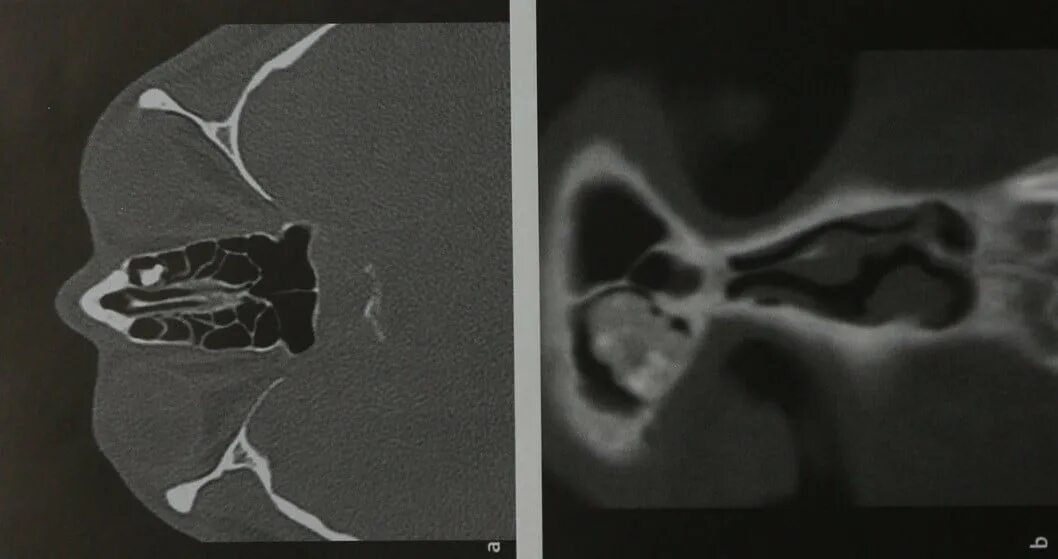

Остеома мрт